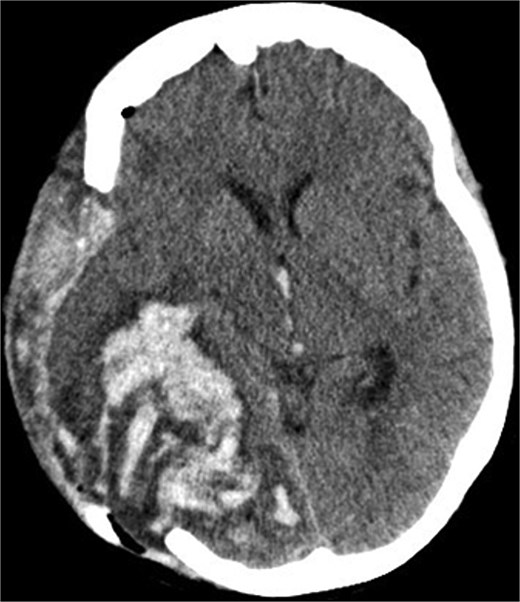

Due to elevated intracranial pressure caused by subdural and subarachnoid hemorrhage, an osteoclastic craniotomy was performed to evacuate the hematoma and relieve pressure (Fig. 2a and b). A large volume of blood was released during trepanation, necessitating intraoperative blood transfusion. Injury to the superior sagittal sinus during the procedure resulted in significant bleeding (Fig. 3), which was managed pharmacologically with the administration of clotting agents. The excised bone flap was sent for histological analysis, which was negative for bacterial infection.

Postoperative axial CT scan. After osteoclastic craniotomy, a large bony defect with parenchymal hemorrhage and additional hemorrhage in the right parietal region is evident.